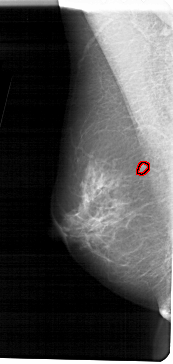

A_1373_1.RIGHT_CC

LEFT_CC LINES 5491 PIXELS_PER_LINE 2341 BITS_PER_PIXEL 12 RESOLUTION 43.5 OVERLAY

FILE: A_1373_1.LEFT_CC.OVERLAY

TOTAL_ABNORMALITIES 1

ABNORMALITY 1

LESION_TYPE MASS SHAPE OVAL MARGINS CIRCUMSCRIBED

ASSESSMENT 3

SUBTLETY 4

PATHOLOGY BENIGN

TOTAL_OUTLINES 1

BOUNDARY